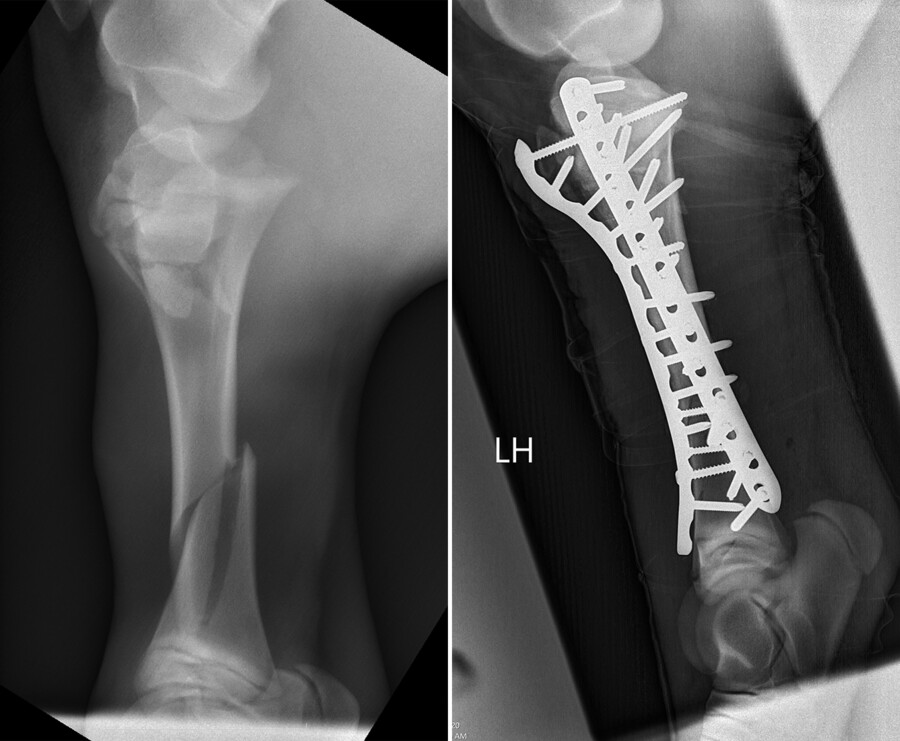

Recently, this place was with Osada, a two-month-old Friesian with a left tibial fracture.

“It was a really severe fracture that was complicated by a second fracture at the growth plate at the top of the bone,” says Ortved. “In foals we usually see one or the other but rarely both. I knew it would be a bit more challenging to repair.”

Osada was placed under general anesthesia. Two long, locking compression plates were carefully screwed into the bone in two places, a fracture repair approach for humans that Richardson adopted for equines early in his career.